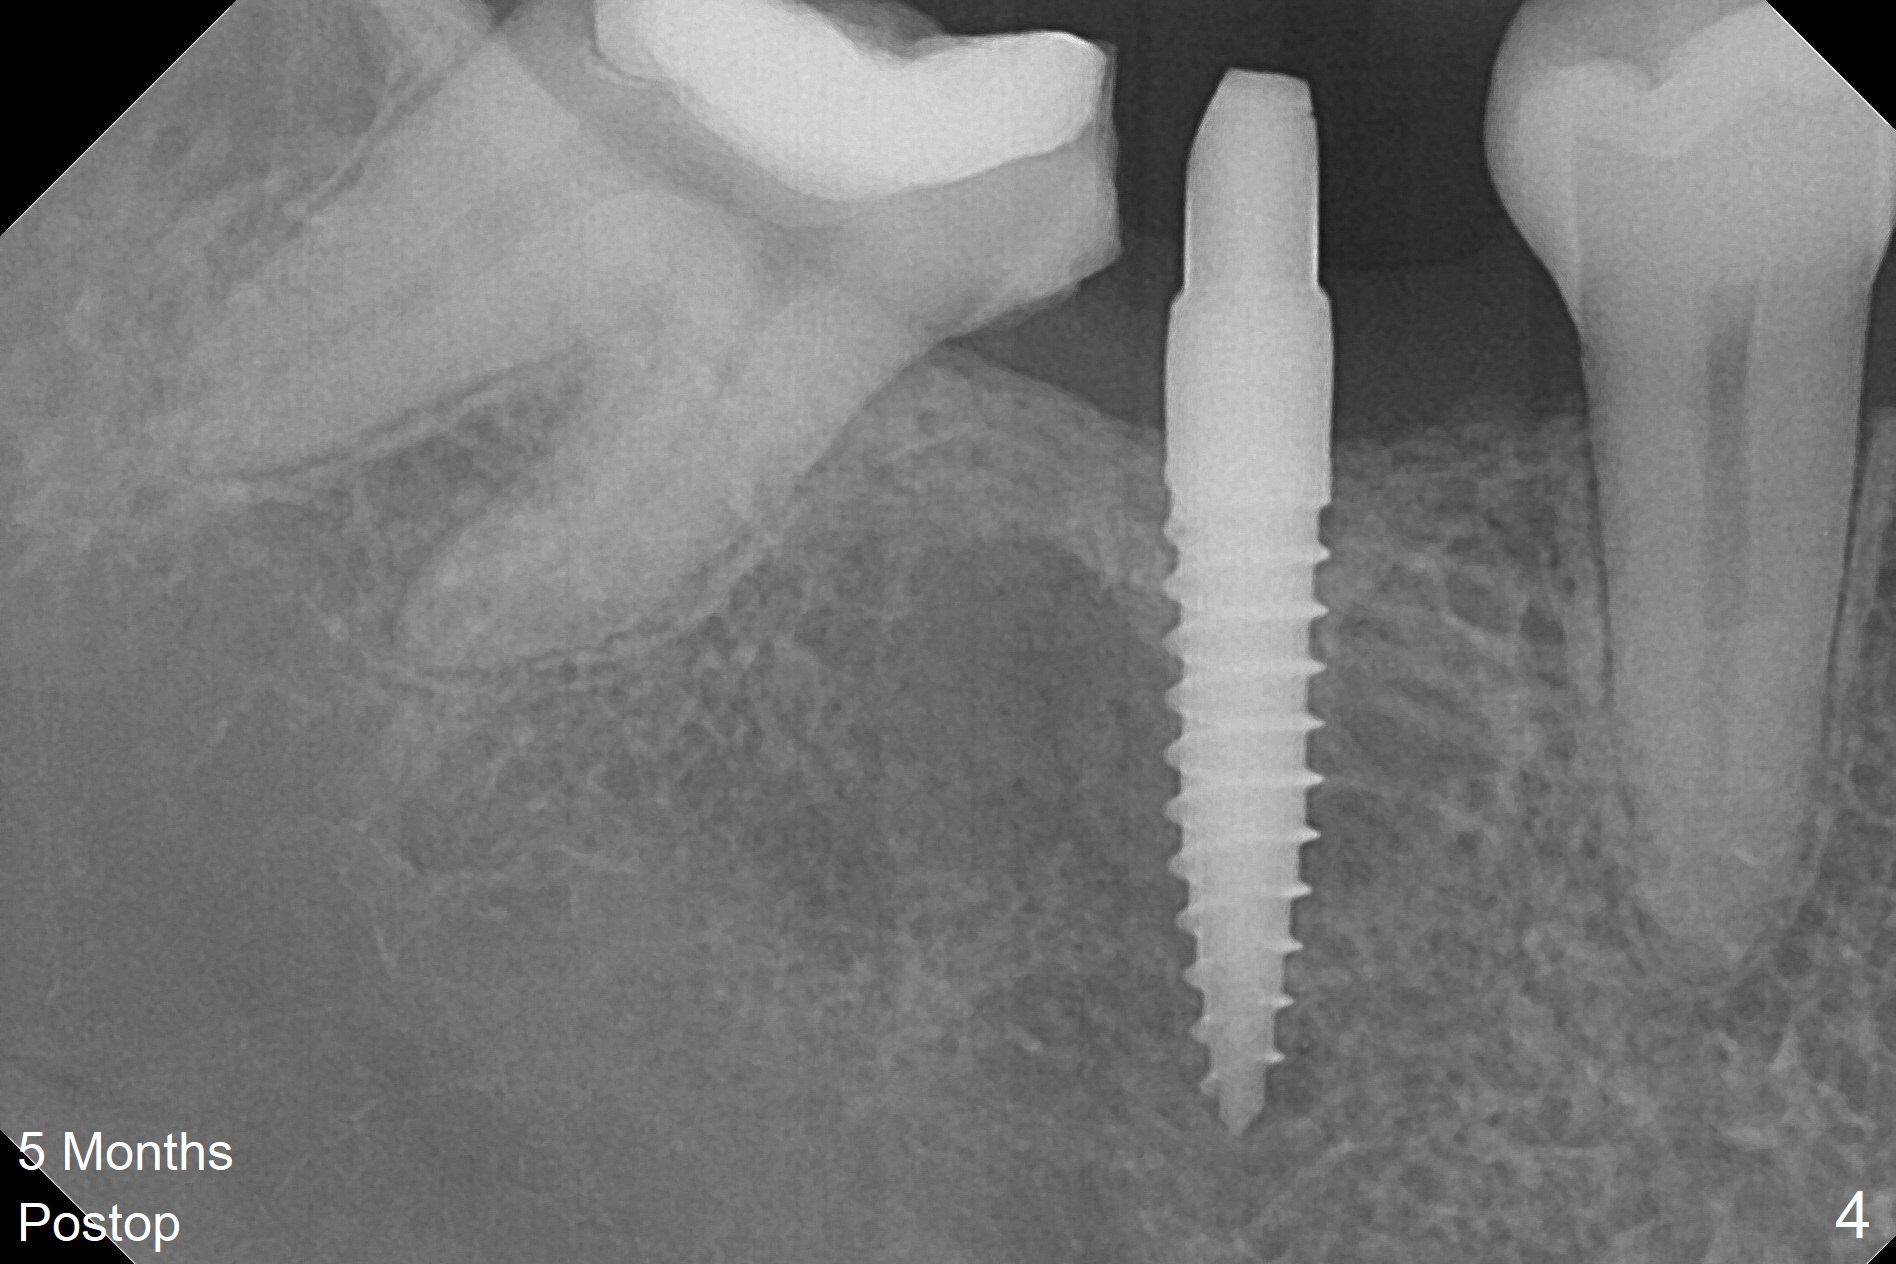

When a 1.2x12 mm drill is placed at #30, it passes the bone cavitation (Fig.1 red dashed line (low density)) twice for two-pointed fixation. So does the 3x12(2) mm 1-piece implant (Fig.2,3). The mesial margin of the tooth #31 is further reduced prior to suturing and periodontal dressing. Impression is taken 5 months postop (Fig.4). Residual cement mesial to the crown at #31 is later removed (Fig.5). Since the crowns were made at #30 and 31 at the same time, there appears no food impaction in between (Fig.6, 5.5 months post cementation).